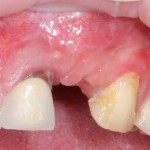

Давайте внимательно посмотрим на состояние лунок центральных резцов после удаления:

Приемлемый фенотип (сочетание толщины и ширины участка жевательной десны) — это, конечно, приятно. Но гораздо важнее сосредоточиться на рисках, их на этот момент два:

— травматическое повреждение слизистой, вызванное удаление зубов связано с тем, что при хроническом воспалении слизистая оболочка теряет эластичность, поэтому легко рвётся. Такая ситуация создаёт серьёзную угрозу эстетическому результату лечения, в зависимости от того, насколько быстро десна придёт в норму.

— как и предполагалось после КЛКТ, утрата костной стенки привела к тому, что десна провалилась в просвет лунки левого центрального резца. Это еще больше усугубляет клиническую ситуацию.

Для нас это не было неожиданностью. Зная закономерности изменений тканей при хроническом  воспалении и данные КЛКТ, мы можем довольно точно предсказывать развитие клинической ситуации и соответственно к ней подготовиться. Именно поэтому, помимо обычной немедленной имплантации, мы запланировали аугментацию лунки с помощью биоматериалов и метода трансплантации лоскута (см. предварительные планы лечения).